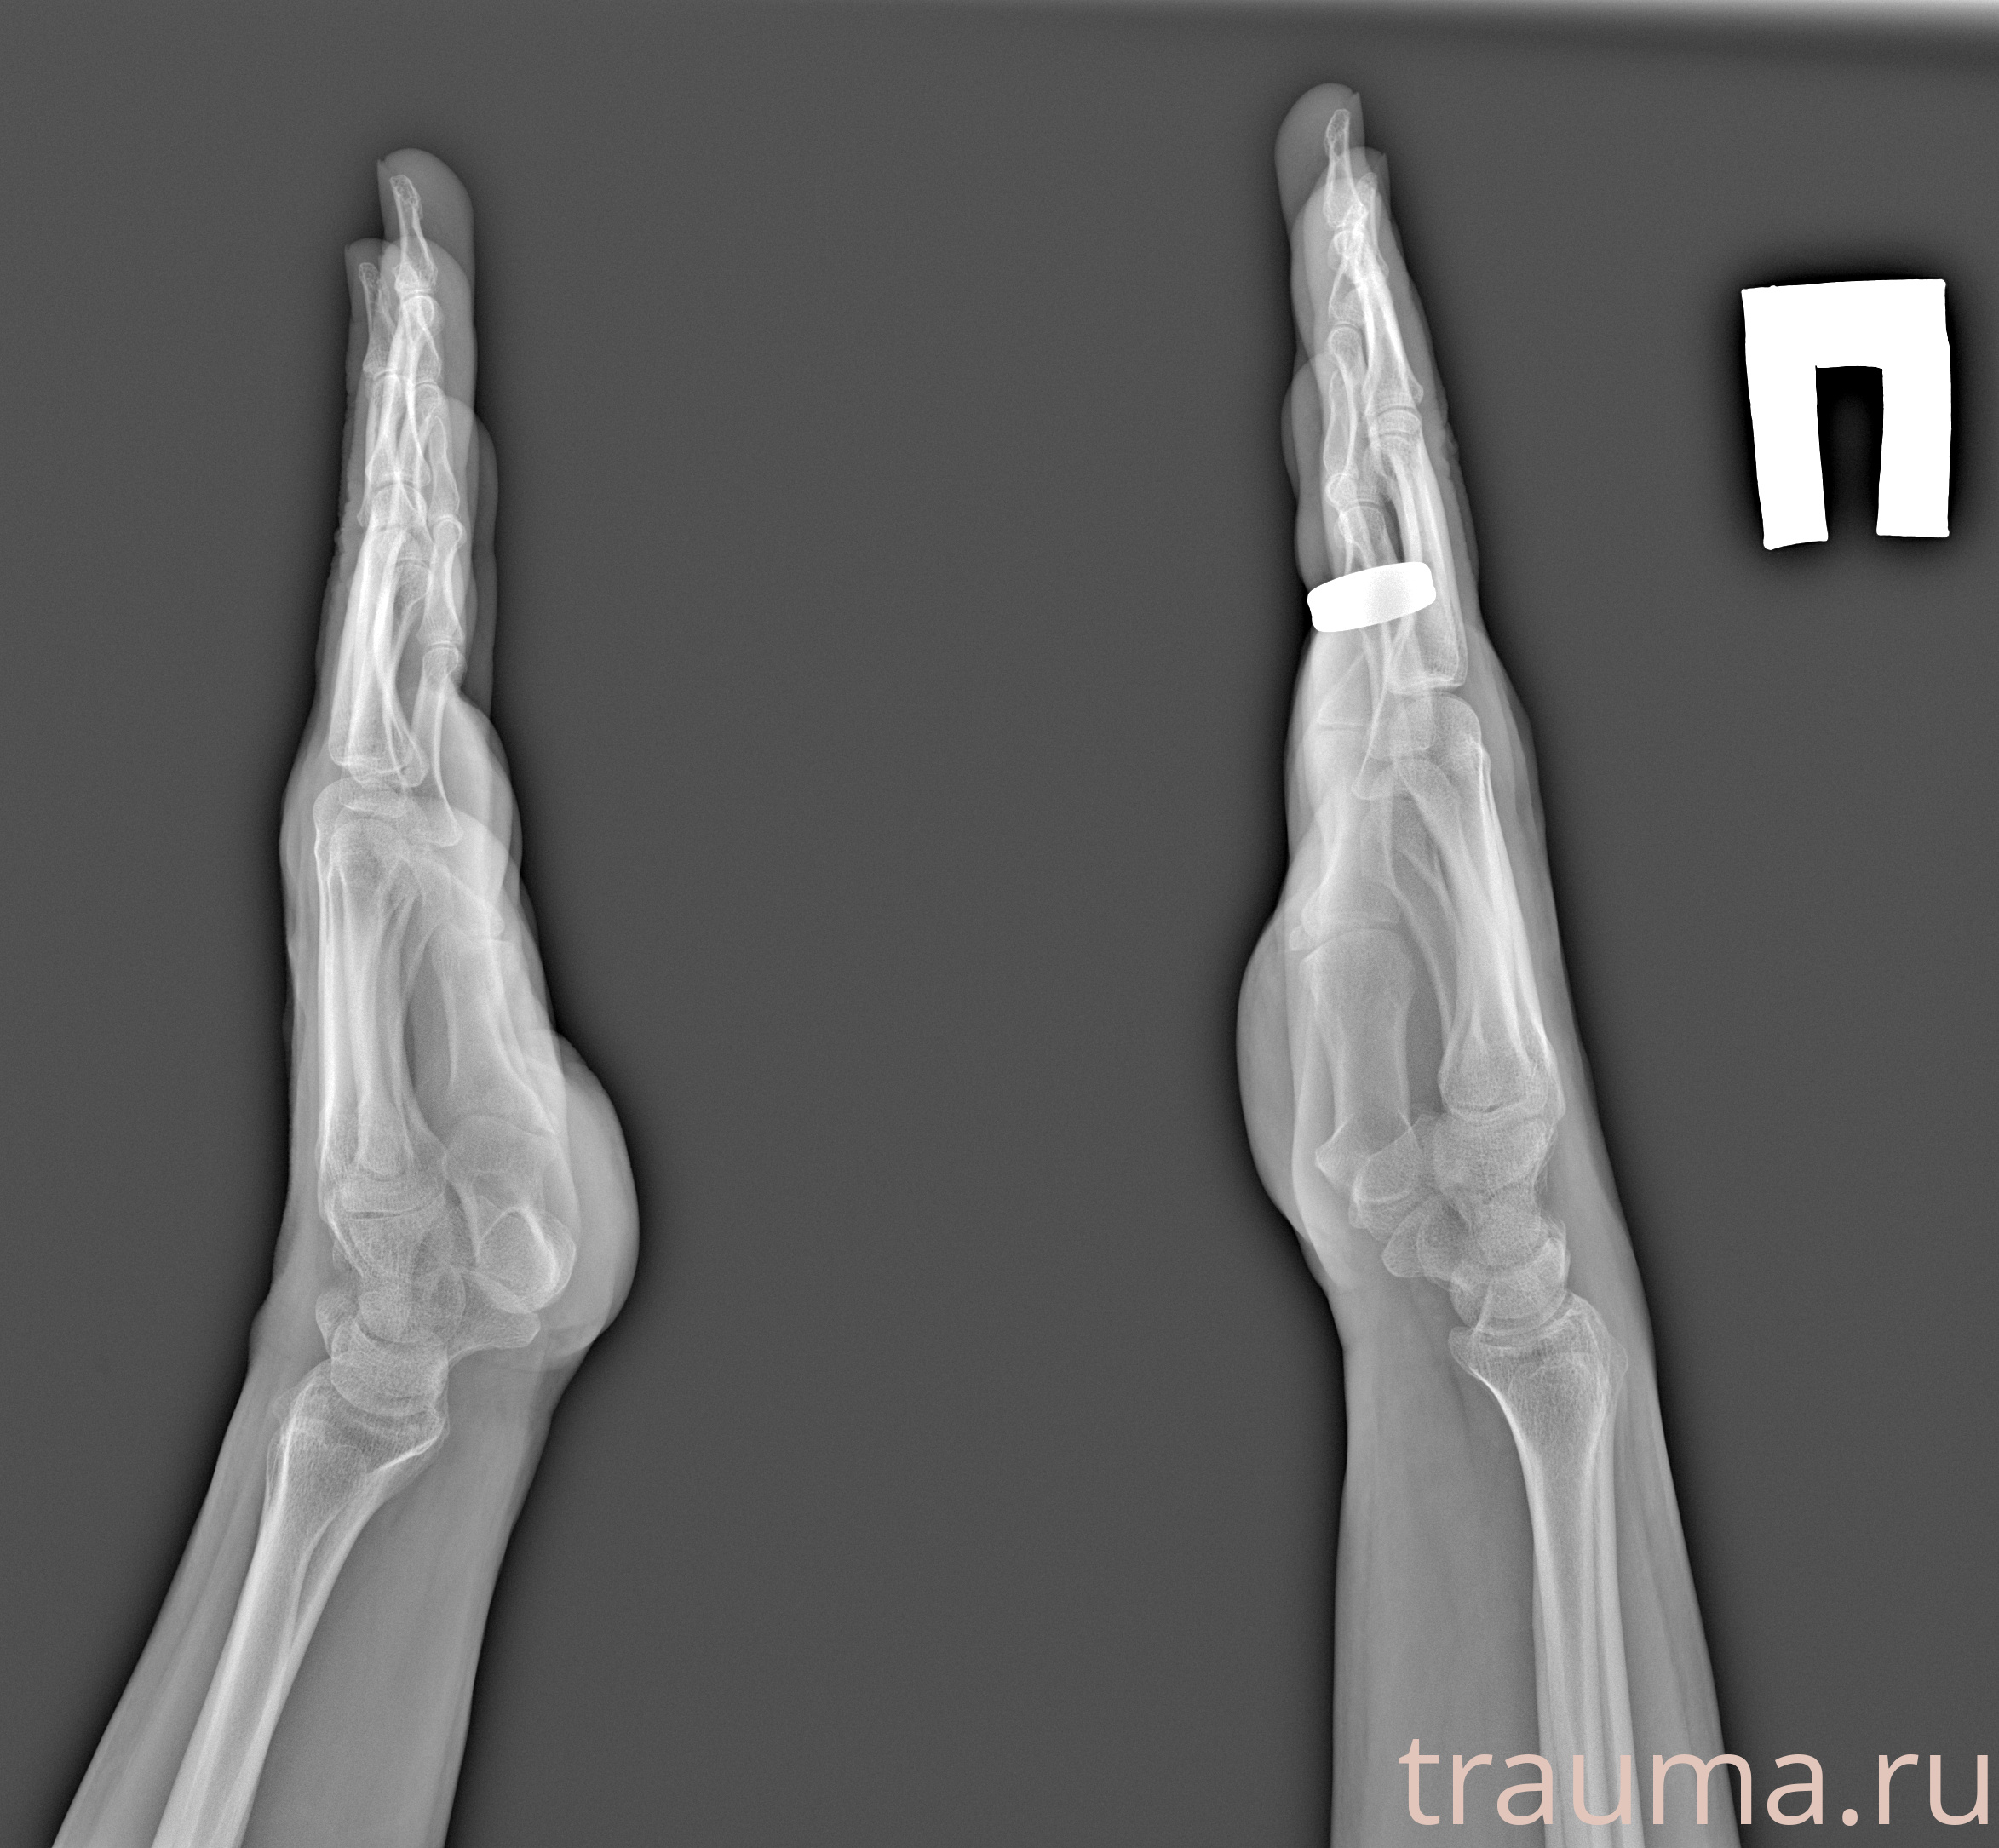

Рентгенограммы

Рентген на дому: по вашему адресу приезжает врач-рентгенолог, травматолог-ортопед с мобильным рентгеновским аппаратом, проводит диагностику травмы или заболевания, делает необходимые рентгенограммы, дает рекомендации по дальнейшему лечению. Получить качественные снимки в домашних условиях возможно благодаря уникальной методике, разработанной МосРентген Центром для института  Склифосовского